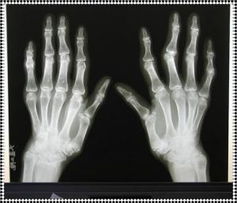

风湿性疾病的病因目前还不明了,不过可以清楚的是风湿性疾病是一组以内科治疗为主的肌肉骨骼系统疾病,包括弥漫性结缔组织病及各种病因引起的关节和关节周围软组织,包括肌肉、肌腱、韧带等的疾病。

2.如果风湿性疾病得不到正确合理的治疗,关节,肌肉,骨骼等病变会导致功能障碍和畸形,留下终身残疾,影响生活和劳动,给个人和社会带来经济损失。从风湿性疾病侵犯的组织看,以往称之结缔组织病的系统性红斑狼疮,类风湿性关节炎,硬皮病,多发性肌炎,坏死性血管炎、强直性关节炎都有自身的紊乱,属于自身紊乱的一组疾病。痛风性关节炎已明确是嘌呤代谢紊乱而导致尿酸盐结晶在关节内沉积,往往有关节腔,骨骼,韧带受累。因此风湿病的治疗除了对症治疗缓解症状外,还需进行病因治疗,自身紊乱性的疾病需要调节,例如使用皮质激素以及抑制剂,抑制疗法有了很大的进步,新药物不断发现,用于临床,如骁息、爱诺华、帕夫林,新疗法不断发现,如①对轻型的系统性红斑狼疮采用小剂量强的松、氯喹、MTX的联合治疗,可以明显减轻副作用;②类风湿性关节炎采用联合治疗,一线药与二线药的联合治疗,二线药之间的联合治疗。③大剂量丙种球蛋白治疗重症风湿病。